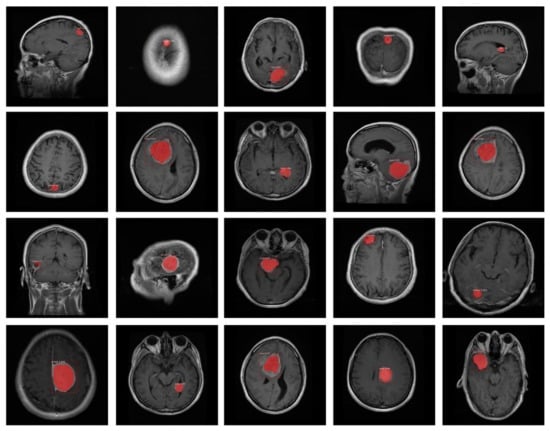

- We have created the annotations which are essential for the training of the proposed model because available datasets do not have a bounding box and mask ground truths (GTs).

- The accurate localization and segmentation of tumor regions due to an effective region proposal network of DenseNet-41-based Mask-RCNN as it works in an end-to-end manner.

3.2. Annotations